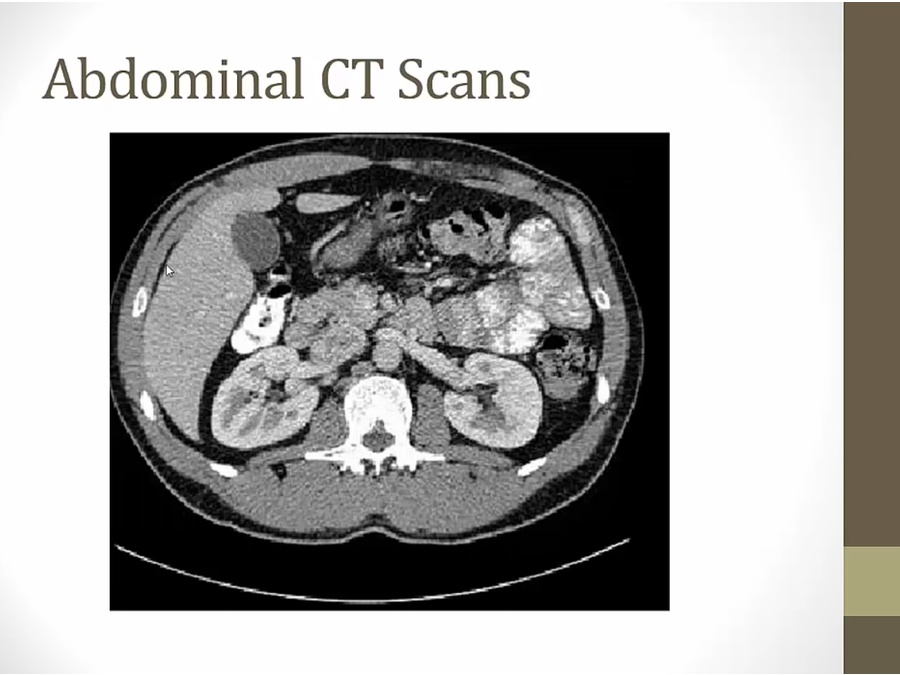

lower in abd

liver with gallbladder (darker)

anterior: intestine and colon with contrast/air

spleen intraperitoneal

grey: hematoma